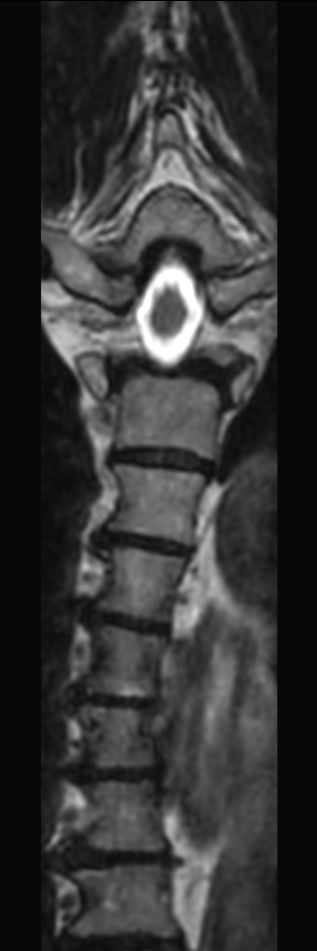

Sagittal T1w TSE (2 stations)Compressed SENSE